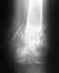

У мальчика (15 лет) застарелый(год) отрыв внутреннего надмыселка левой плечевой кости. Рука функционирует, но есть ощущение дискомфорта и физические нагрузки приходится ограничивать. Врачи пока не могут принять решение: оперировать или нет. Как лучше поступить, чтобы не навредить?

Травма произошла больше года назад в ортопедическом санатории "Люстдорф", Одесса. Мальчику наложили шину. Не оперировали. После того, как гипс был снят, он пошёл на тренировку и снова травмировался. Врач, к которому обращались, поставил неправильный диагноз: растяжение связок, рентген не посчитал обязательным. Посоветовал подождать несколько месяцев, пока всё восстановится. Спустя год сделали рентген, который показал начальный диагноз (установленый в Одессе)- отрыв внутреннего надмыселка левой плечевой кости. Ортопеды разошлись во мнениях, что делать дальше. Оторванный кусочек кости опустился. Одни считают, что если рука функционирует, хирургическое вмешательство не обязательно. Другие говорят о необходимости операции во избежание возможных новых травм. Но и те, и другие сомневаются. Мальчик пока не может заниматься спортом. Боится нагружать руку. Как нам поступить? Рентгеновские снимки пока находятся у врача.

Хотелось бы увидеть рентгенограммы.